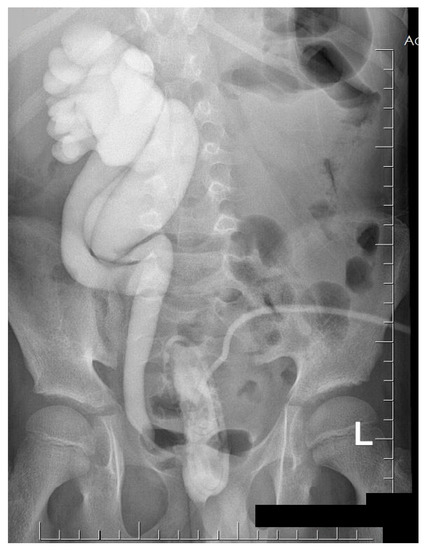

A cystourethrography study was performed and showed the fifth grade of vesicoureteral reflux and duplicated collecting system on the right side (Figure 3).

In the publication by Rote et al., the authors suggested that, in the case of renal parenchymal infection with Gram-negative bacteria, the patient should undergo cystourethrography [1]. In our clinic, such a procedure was performed, as it was suspected that the origin of the process ascended from the urinary tract. The presence of fifth-grade vesicoureteral reflux and duplication of the ureter, combined with the abnormalities of the bladder, pointed to the increased risk of ascending UTI [6,8].

Figure 3. The duplicated collecting system and the fifth-degree vesicoureteral reflux on the right side were presented in the micturating cystourethrography.